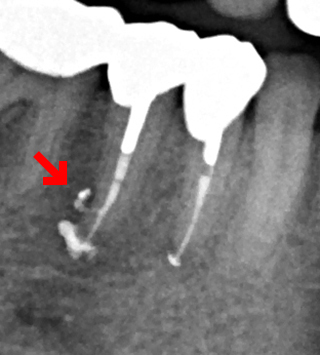

- 右下の歯にうずくような痛みがあると来院。レントゲンで大きな歯根嚢胞を確認。

右下5番は根管に側枝という横穴が開いてそのせいでその部分にも嚢胞がありました。一般的な側方加圧充填ではこの部分は充填剤が入らないため抜歯になってしまうケースです。

垂直加圧根管充填できちっと根尖にも側枝にも充填剤が入りました。側枝に充塡剤がしっかり入っているとこのようにレントゲンに写ります(部分)。処置後3年経過しましたが快適だそうです。